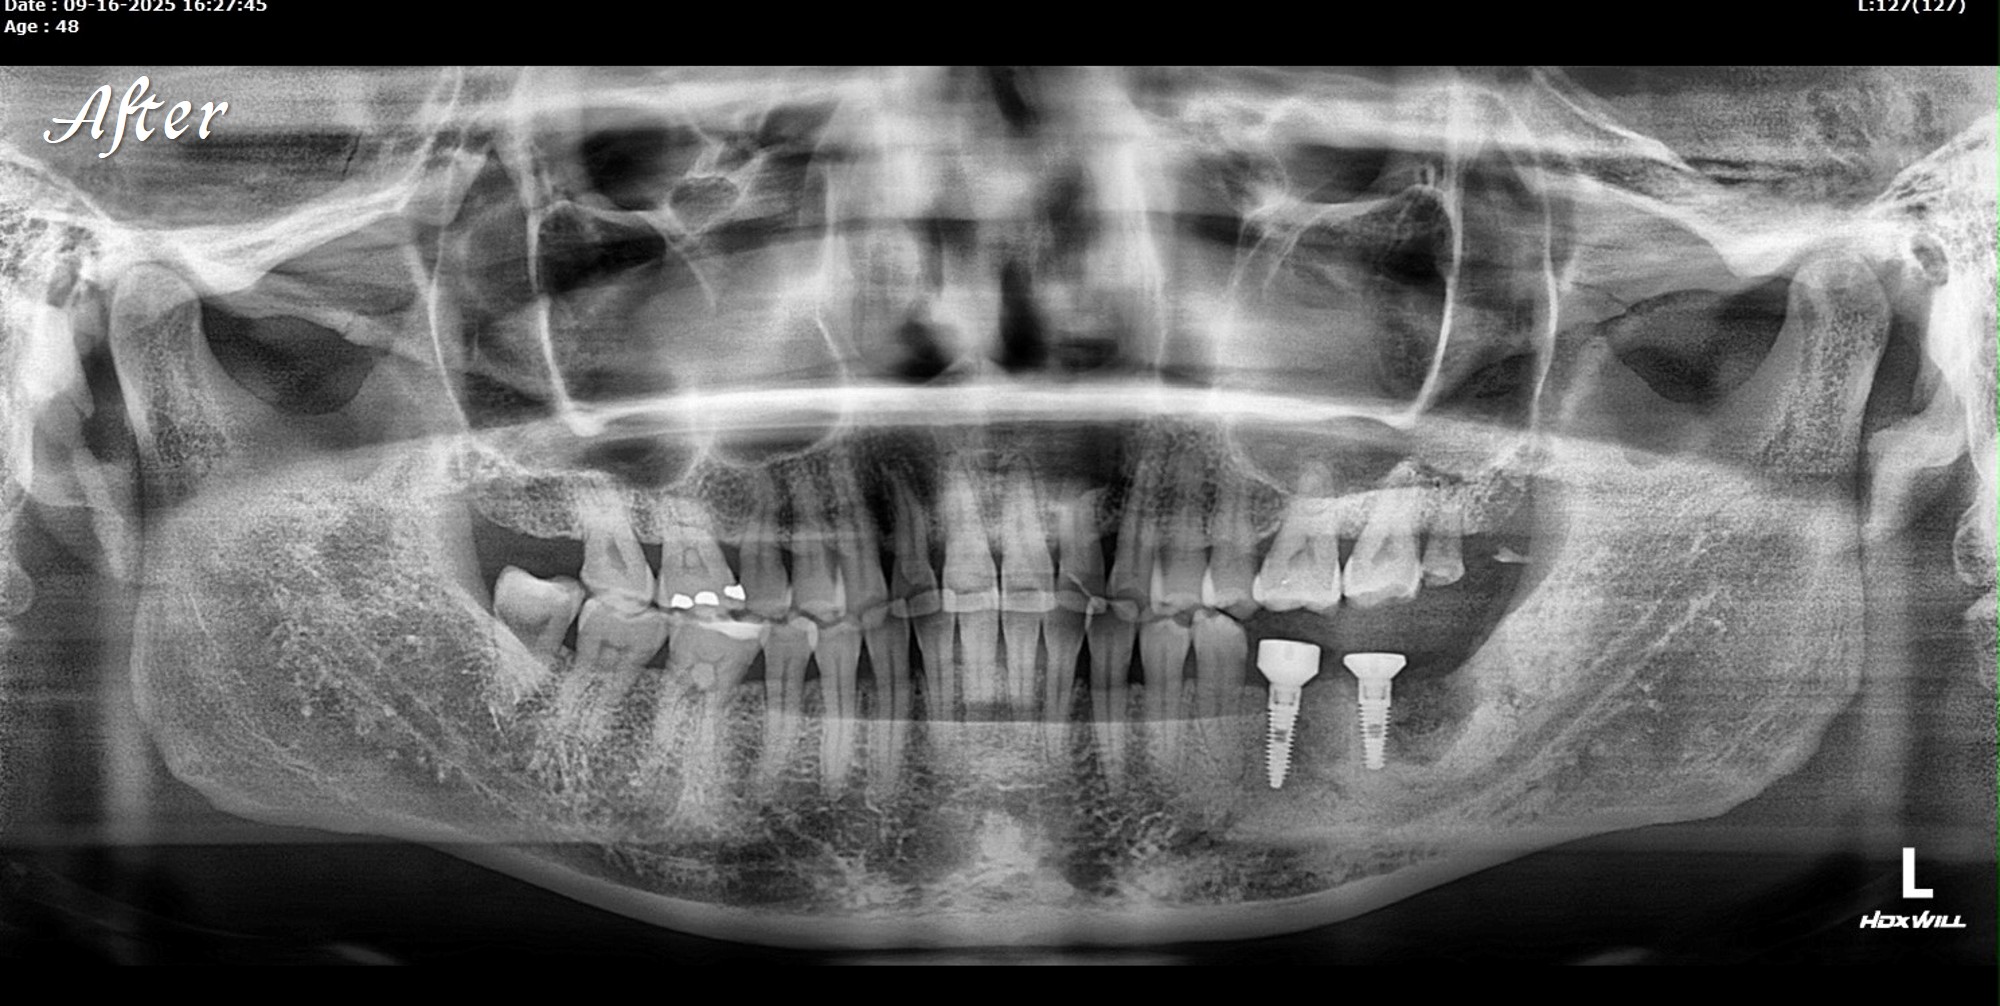

精奈創一鑽植牙系統團隊|3.5個月完成的植牙案例

一位初診新患者,陳博士評估後進行治療。

植牙後約3.5個月骨整合完成,骨頭穩定生長良好。

這樣的恢復速度,與Ezechbone的特性有關,

但最重要的是要有良好的primary stability。

植牙當天,scan body掃描就同步完成,流程一次到位。

接下來就是裝固定假牙。